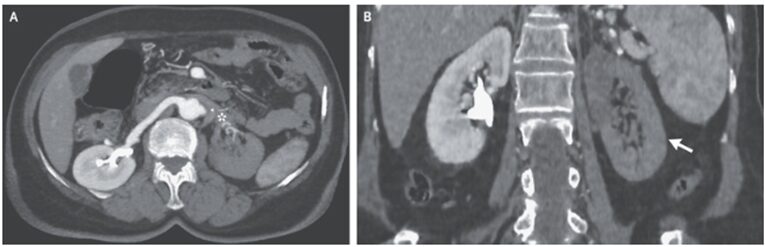

造影CT施行。左腎動脈の造影効果消失を認め、左腎梗塞が示唆された。